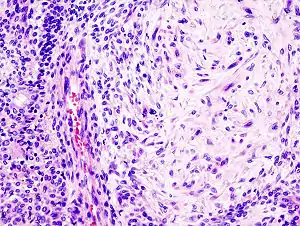

Pleomorphic adenoma consists of mixed epithelial (left) and mesenchymal cell components (right). The latter often exhibits myxofibrous appearance and in some instances shows chondromatous differentiation.

Morphological diversity is the most characteristic feature of this neoplasm. Histologically, it is highly variable in appearance, even within individual tumors. Classically it is biphasic and is characterized by an admixture of polygonal epithelial and spindle-shaped myoepithelial elements in a variable background stroma that may be mucoid, myxoid, cartilaginous or hyaline. Epithelial elements may be arranged in duct-like structures, sheets, clumps and/or interlacing strands and consist of polygonal, spindle or stellate-shaped cells (hence pleiomorphism). Areas of squamous metaplasia and epithelial pearls may be present. The tumor is not enveloped, but it is surrounded by a fibrous pseudocapsule of varying thickness. The tumor extends through normal glandular parenchyma in the form of finger-like pseudopodia, but this is not a sign of malignant transformation.